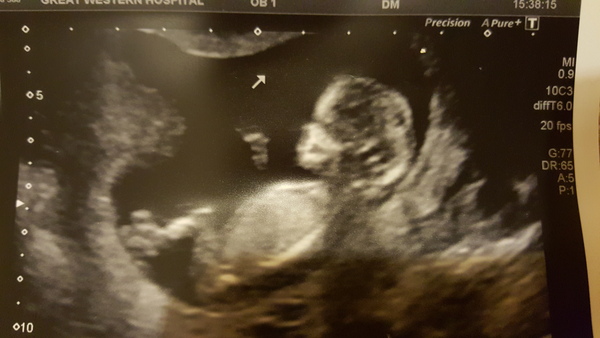

Gorgeous scan pics MrsLewis & LouLou! My scan went well - due date still 20th June & baby gave us a little wave Smile

Scan went well! Although baby was sleeping so reluctant to move into the right place, had to do a lot of wriggling myself! We did get a wave and a yawn however!!